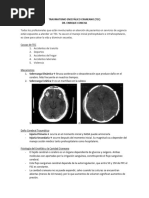

D. TAC CEREBRAL Predice riesgo HTEC y

mortalidad

Desviación 5 mm línea media

Estado de Cisternas Basales

Lesiones focales >20 ml (ABC/2)

Contusiones cerebrales (empeora

50%)